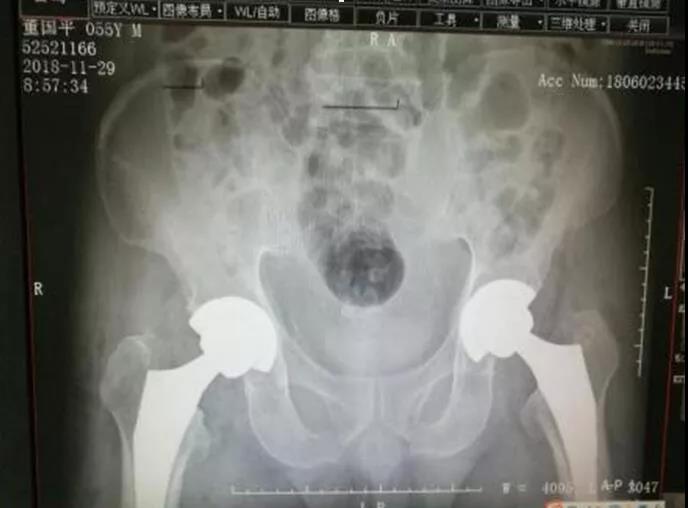

刘主任最终决定改变传统的后外侧手术入路方式,采用仰卧位直接前入路全髋关节置换术。术中不用改变患者体位,可一次性行双侧全髋置换。

▲术后DR片